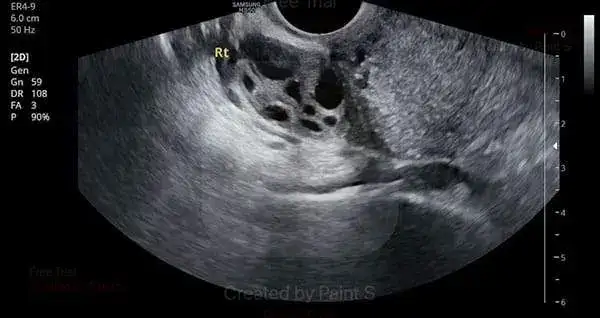

Polikistik Yumurtalık | Çok sayıda küçük kist içerir | ❌ Kroniktir, kontrol gerekir |

Düzenli takip ultrasonla yapılır.